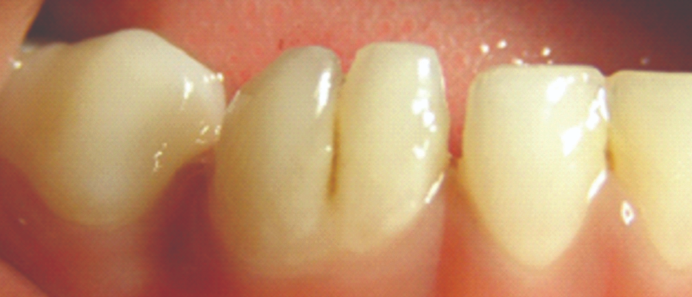

2. 前牙的畸形舌侧窝沟